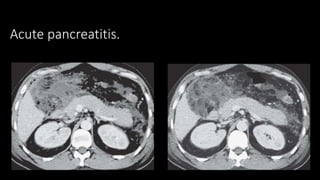

 Acute pancreatitis

 Role of CECT

 CT findings

Acute pancreatitis.

Severe pancreatitis.

• Fluid collection

• Pancreatic necrosis

• Haemorrhage

• Pseudocysts

• Pseudoaneurysms

• Venous thrombosis